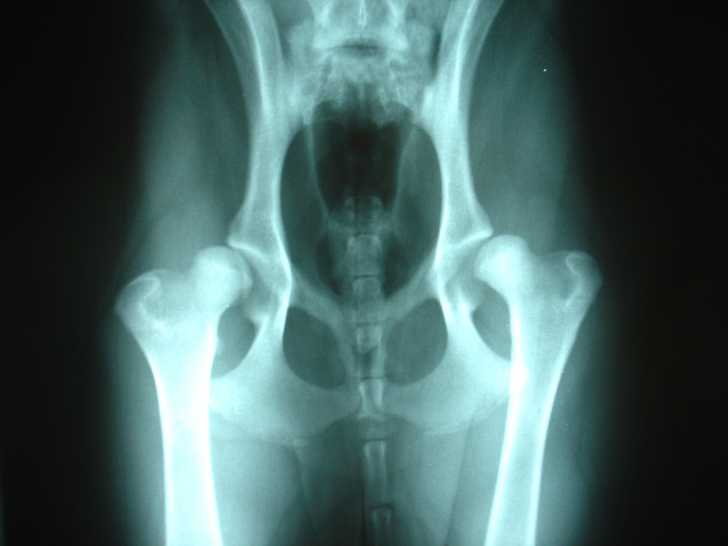

Par exemple, la dysplasie coxo-fémorale touche en général les grands chiens de moins de deux ans. Cependant, les autres peuvent également être concernées par cette malformation génétique qui se développe au fil de la croissance. Il s'agit d'une anomalie héréditaire qui touche la tête du fémur et la cavité de la hanche où elle s'emboîte. Le chien commence à souffrir vers un an. Il présente des difficultés au niveau de la marche, refuse de sauter et a du mal à courir.

Le traitement de la dysplasie de la hanche varie en fonction des caractéristiques physiques de l'animal. Ainsi, chez les petits chiens, c'est une résection de la tête fémorale qui est généralement pratiquée. En revanche, chez les grands, l'articulation coxo-fémorale touchée est couramment remplacée par une prothèse adaptée à la morphologie de l'animal.

Au passage, il faut savoir que la dysplasie constitue un vice rédhibitoire lors de l'achat d'un chien ou d'un chiot, et peut, par conséquent, être un motif légitime d'annulation de la vente.